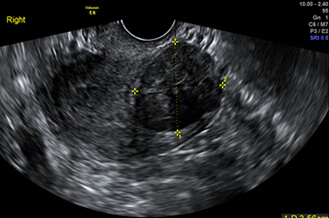

正常子宮